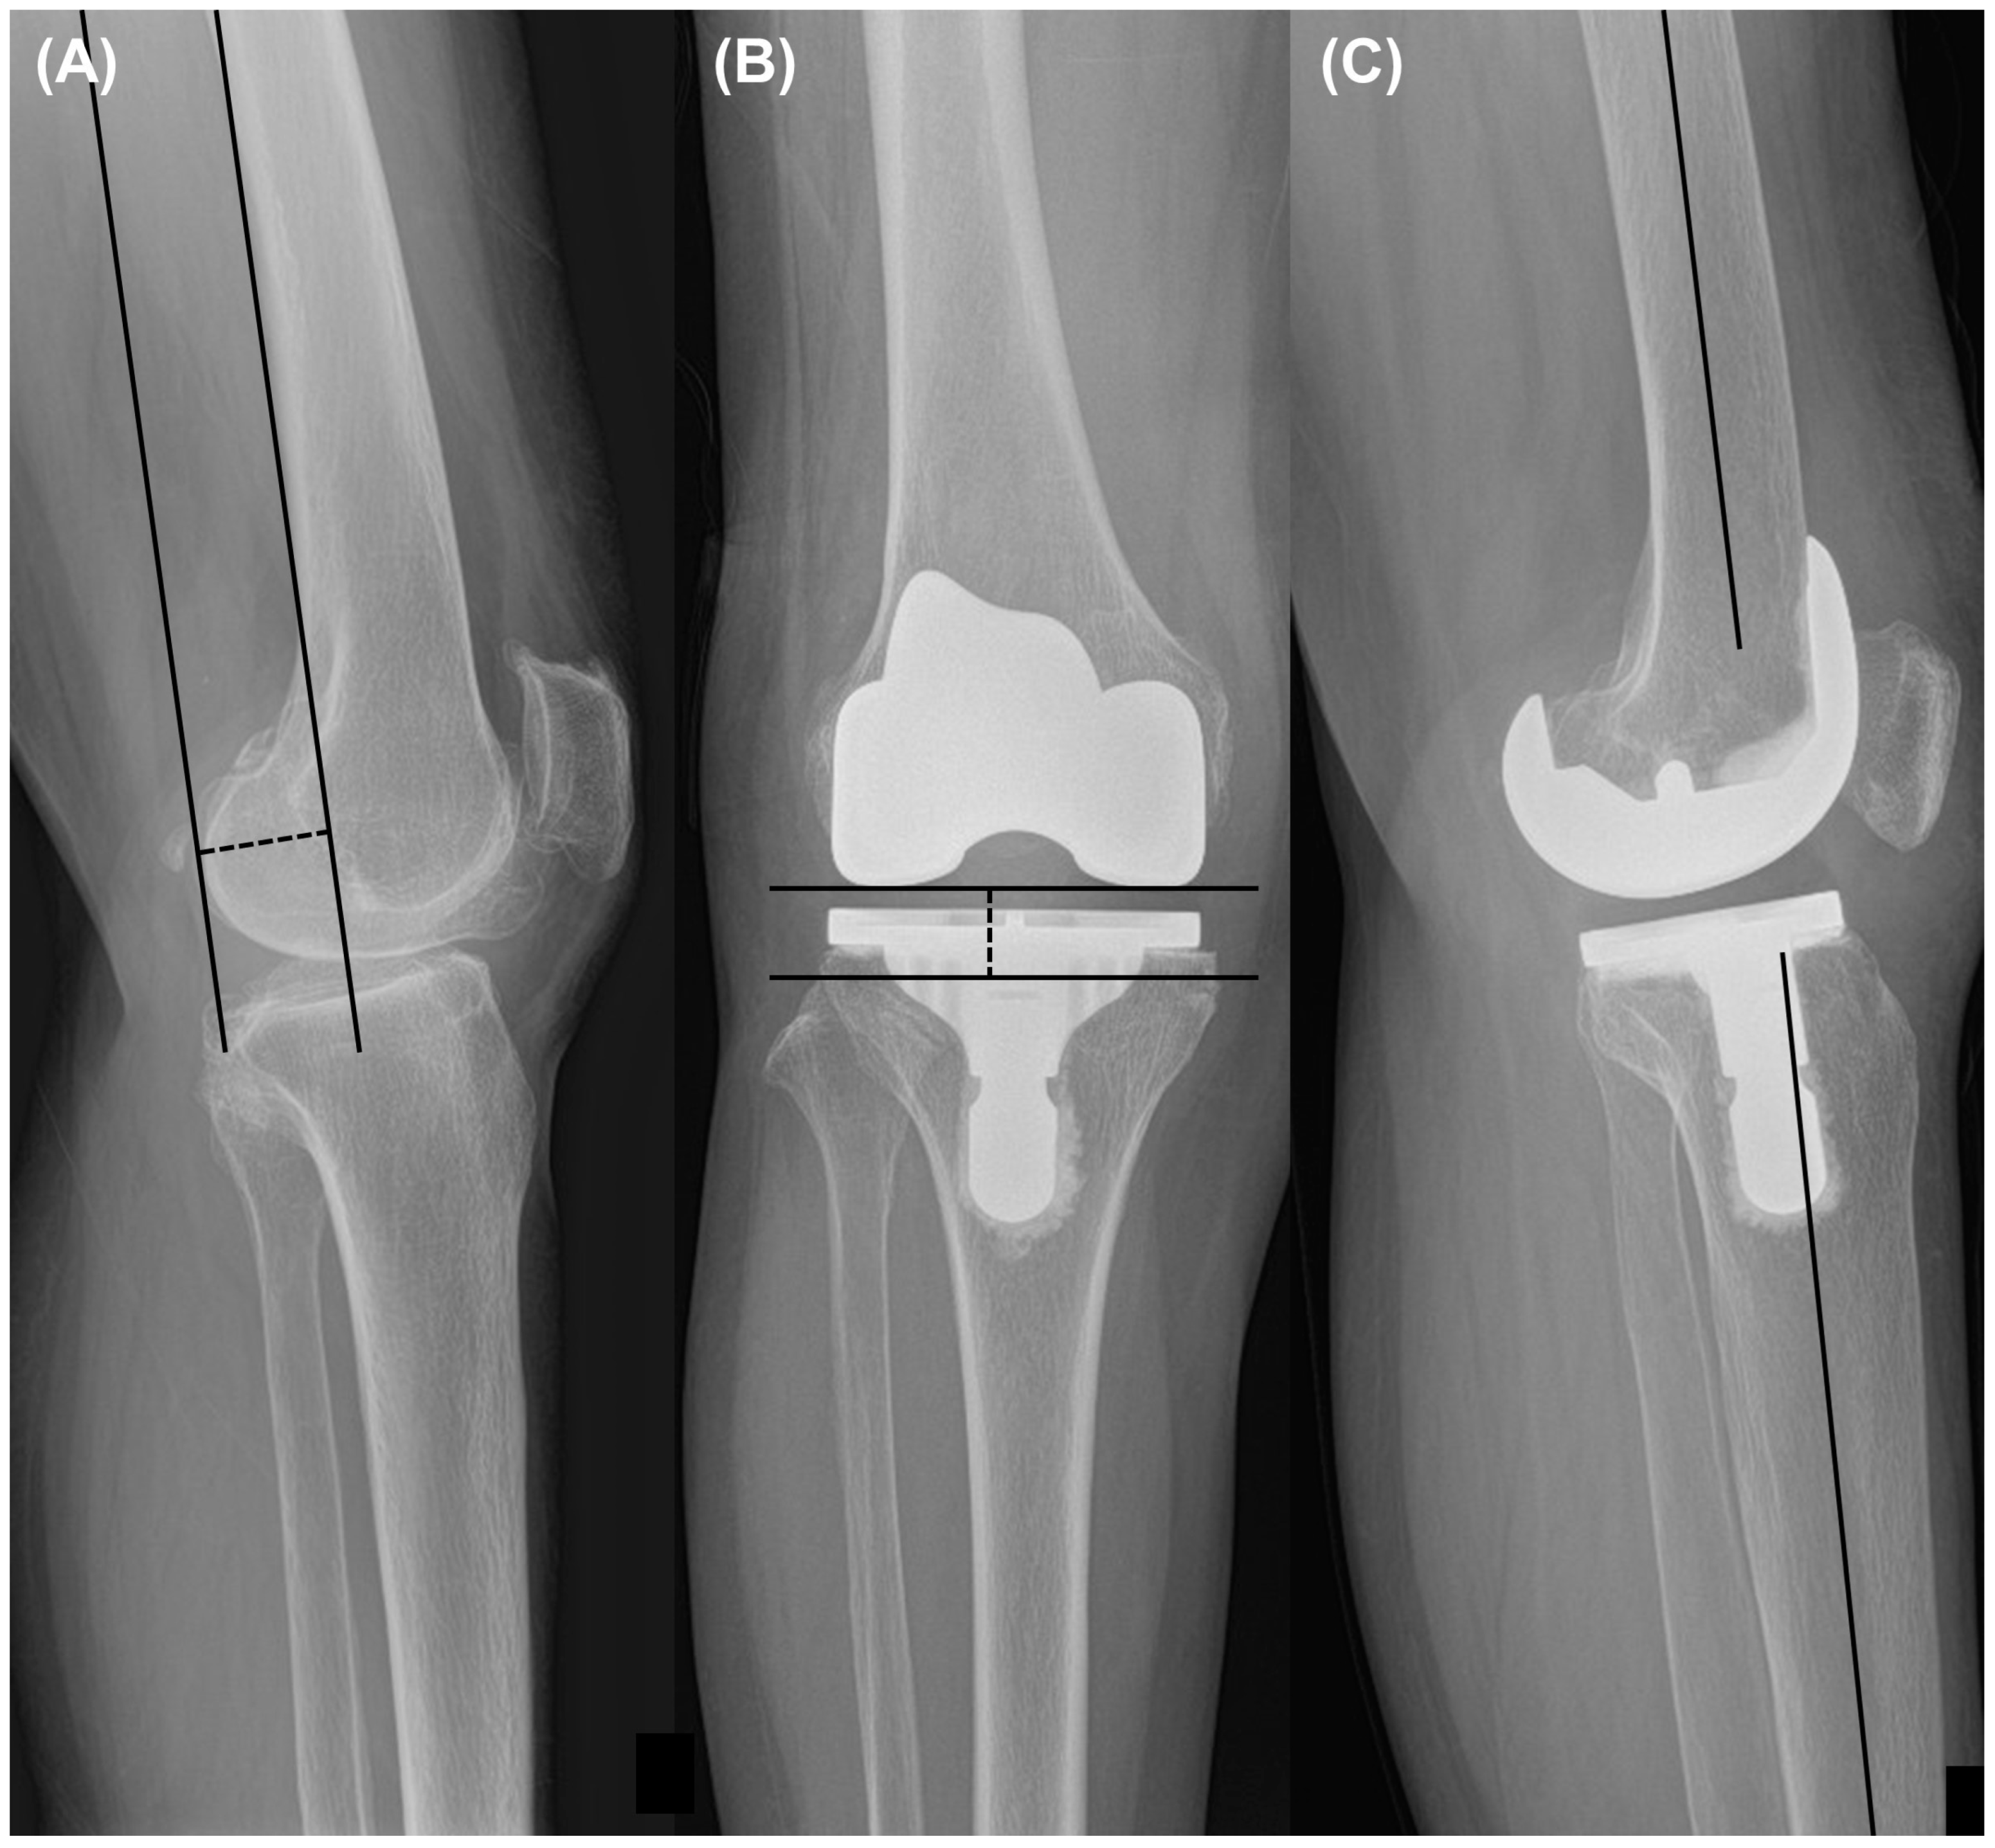

The femoral posterior condylar offset is measured from the posterior condyle to the posterior cortical margin as the distance (Figure 2) [21]. The extension angle on a radiograph was highly reproducible and demonstrated greater accuracy than the measurement on a goniometer [22]. This angle was measured as the angle between the distal femoral axis and the proximal tibial diaphyseal axis, that is, the line connecting the midpoints of the outer cortical diameter at 5 cm and 15 cm proximal or distal to the joint line on the full extension lateral view. It was also measured pre-and postoperatively [21]. A positive value denoted flexion contracture, while a negative value signified hyper-extension. Joint line distances were measured preoperatively and postoperatively as the distance from the apex of the fibular head to the tibial plateau or femoral component, respectively [23].

Figure 2.

Measurement of (A) femoral posterior condylar offset, (B) joint line distance on anteroposterior radiographs, and (C) extension angle on full extension lateral view radiographs.